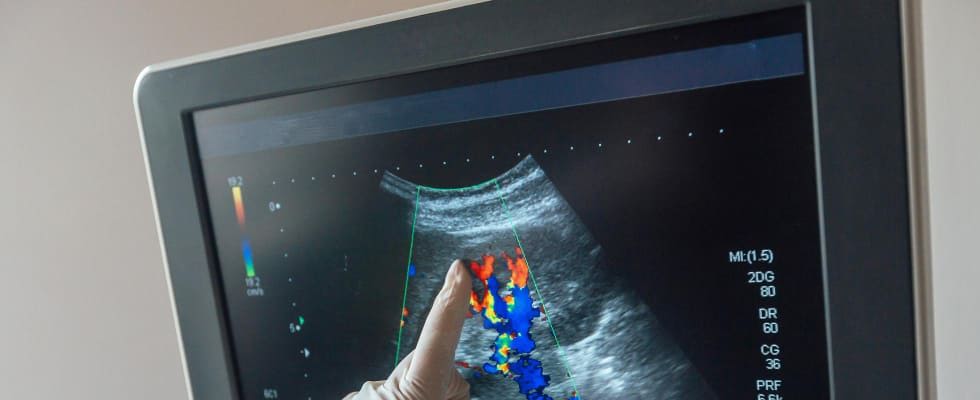

Badanie USG nadnerczy polega na wykorzystaniu fal ultradźwiękowych do wizualizacji nadnerczy. Pacjent leży na plecach, a na skórę w okolicy brzucha nakładany jest żel przewodzący. Następnie głowica ultrasonograficzna przesuwana jest po skórze, emitując fale dźwiękowe, które odbijają się od tkanek i tworzą obraz na monitorze. Dzięki temu możliwe jest dokładne zbadanie struktury i wielkości nadnerczy oraz wykrycie ewentualnych zmian patologicznych. Badanie jest bezbolesne i nieinwazyjne.